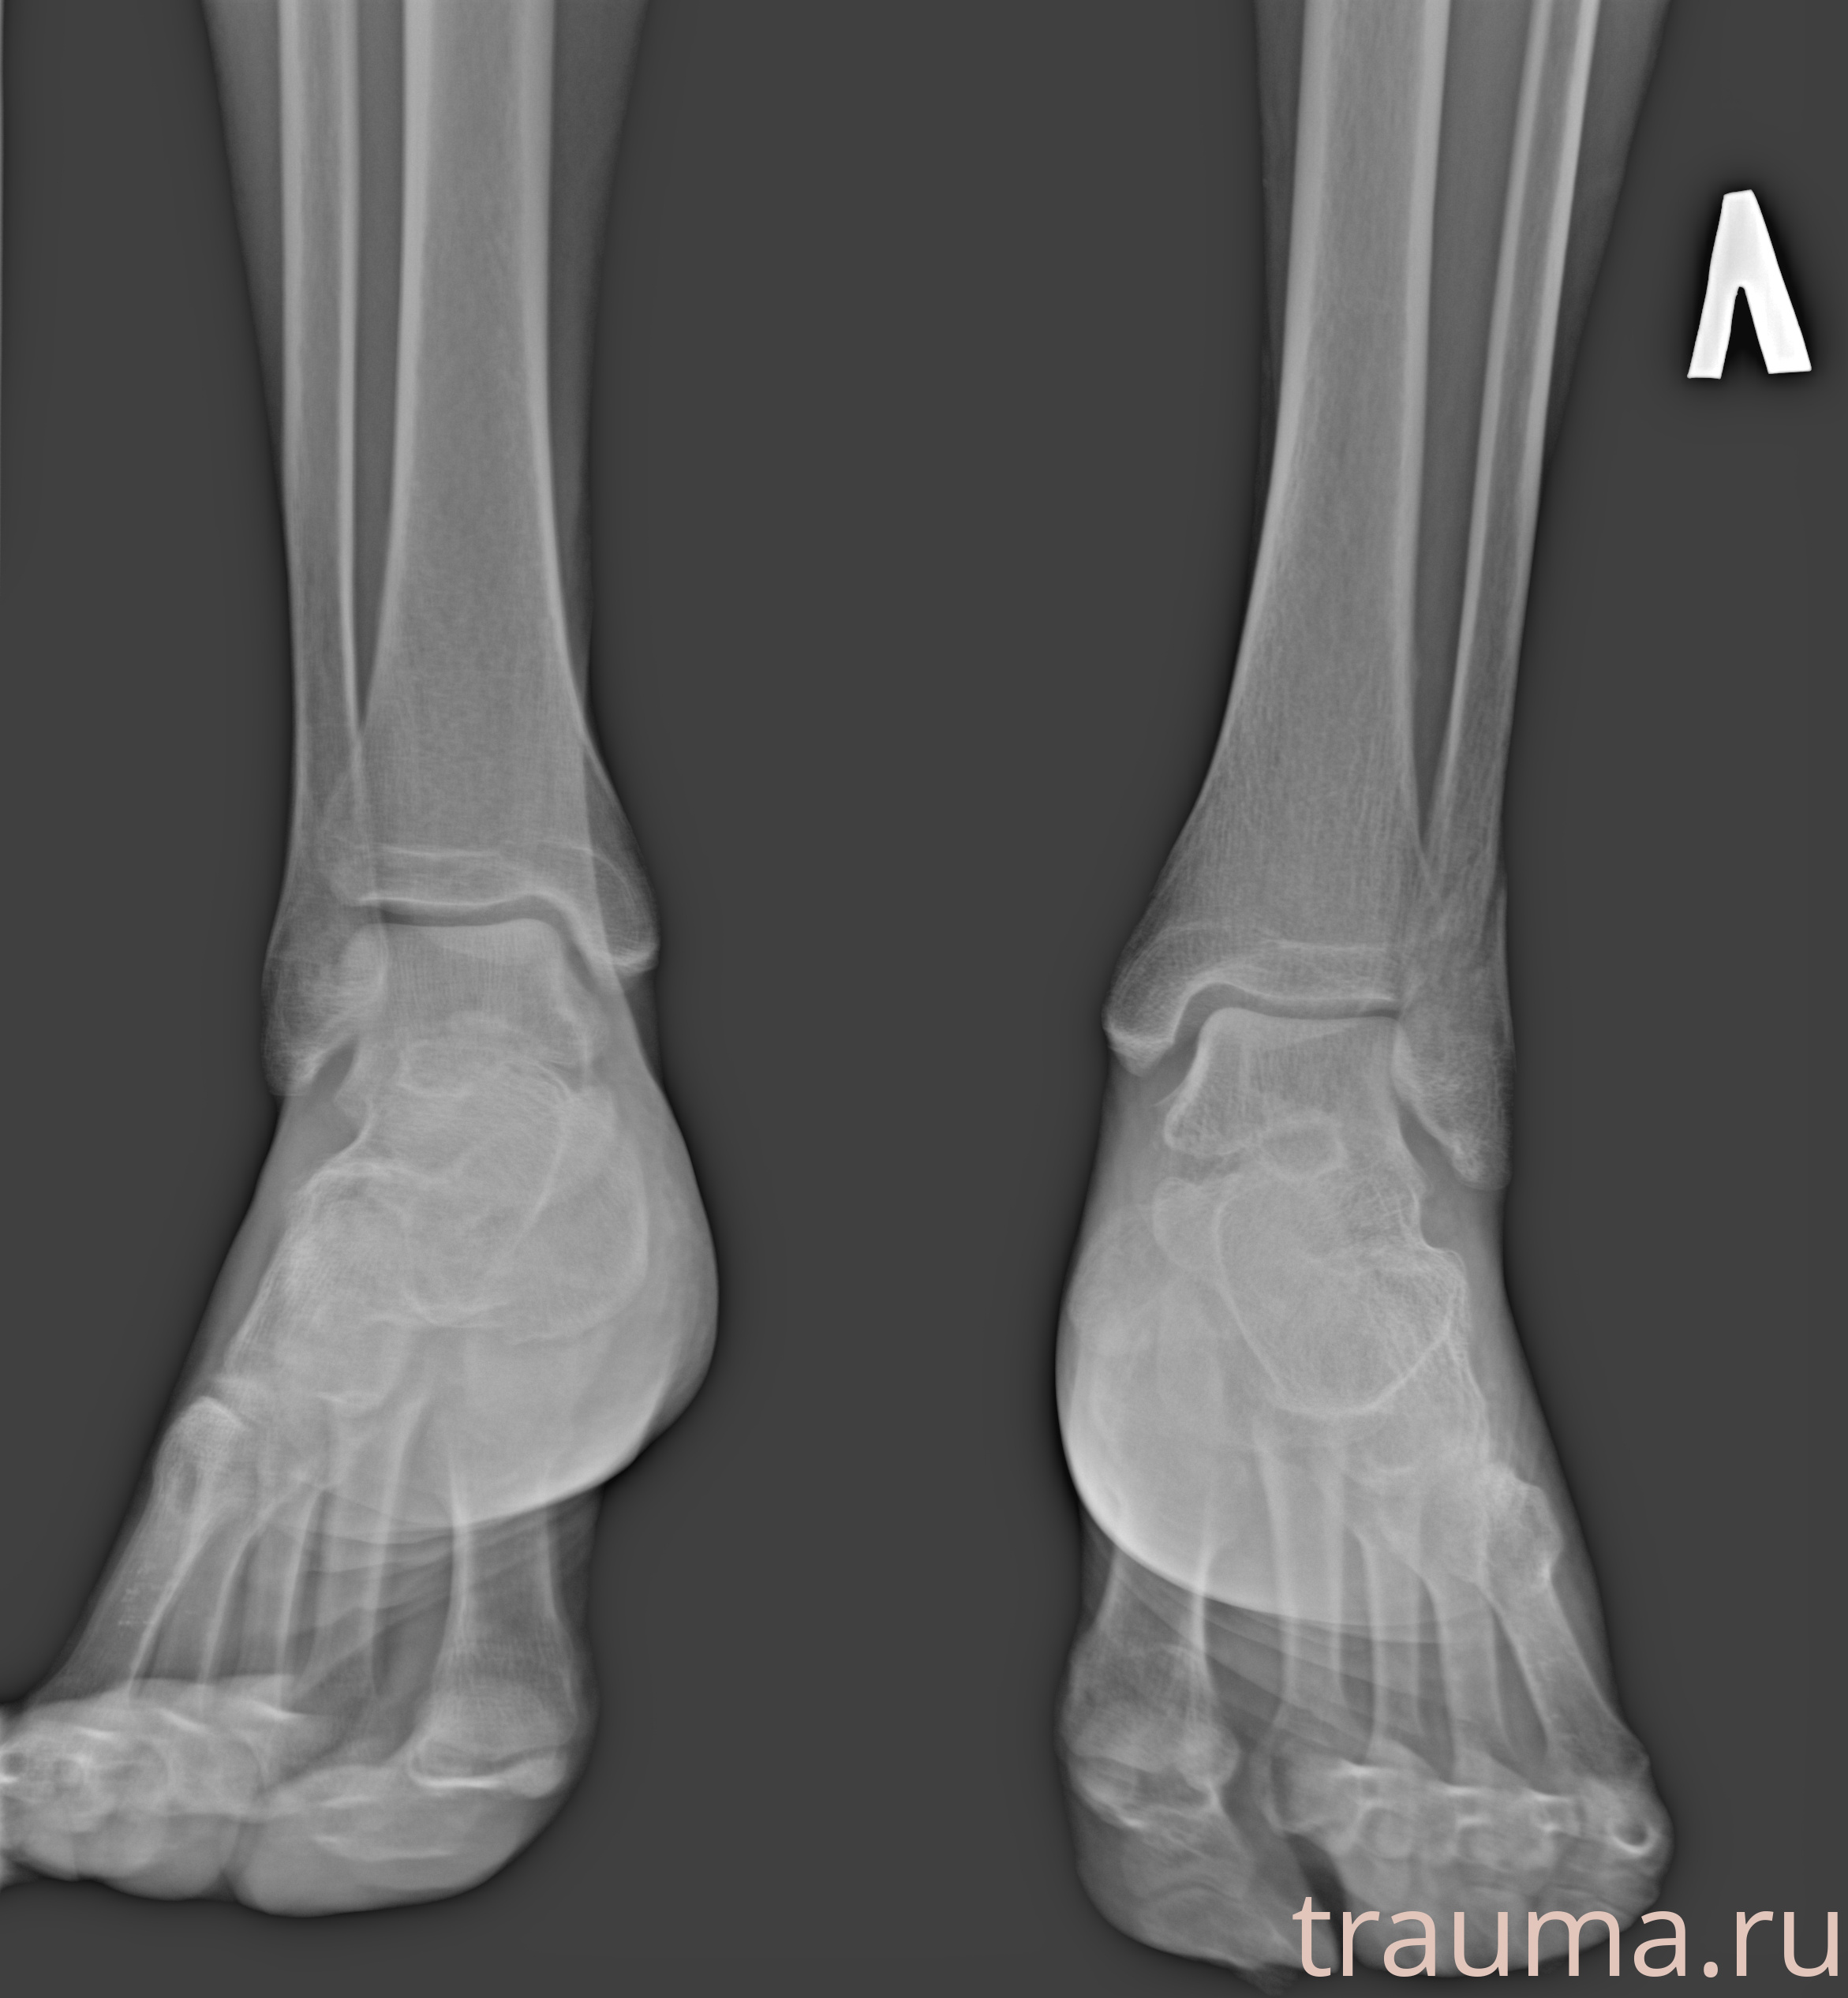

Рентгенограммы

Рентген на дому: по вашему адресу приезжает врач-рентгенолог, травматолог-ортопед с мобильным рентгеновским аппаратом, проводит диагностику травмы или заболевания, делает необходимые рентгенограммы, дает рекомендации по дальнейшему лечению. Получить качественные снимки в домашних условиях возможно благодаря уникальной методике, разработанной МосРентген Центром для института  Склифосовского